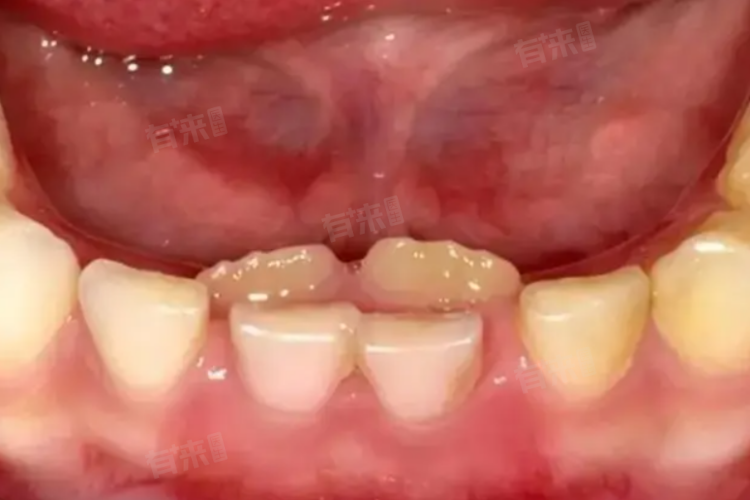

1、饮食习惯改变:现代儿童饮食趋于精细化,如常吃软食、甜食等,缺乏足够的咀嚼刺激,导致乳牙牙根吸收不足,难以自行脱落。新牙(恒牙)因此被迫在乳牙内侧或外侧萌出,形成“双排牙”。鼓励孩子多吃富含纤维的食物,如苹果、玉米、胡萝卜等,增加咀嚼机会,促进乳牙牙根吸收。

4、恒牙牙胚发育异常:恒牙牙胚在发育过程中可能出现异常,如位置偏移、萌出方向错误等,导致恒牙在乳牙未脱落前即已萌出。对于恒牙牙胚发育异常的情况,应观察恒牙萌出的位置和形态,评估其对口腔功能和美观的影响。若恒牙萌出位置明显偏离正常,且影响口腔功能和美观,可考虑在恒牙全部替换完成后进行正畸治疗。